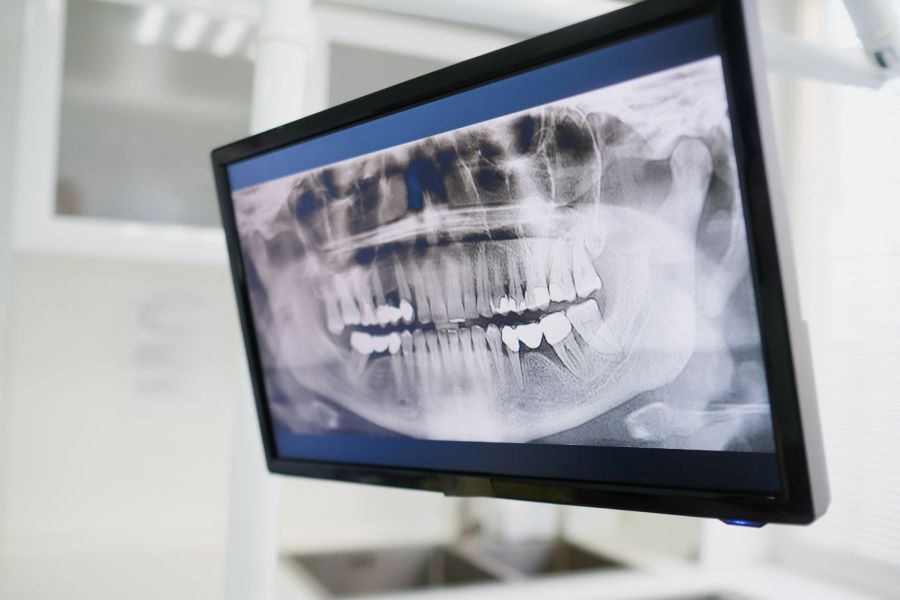

1. Untersuchung & Röntgendiagnostik

Zu Beginn analysieren wir den betroffenen Zahn und erstellen Röntgenaufnahmen, um Verlauf und Anzahl der Wurzelkanäle genau zu bestimmen.